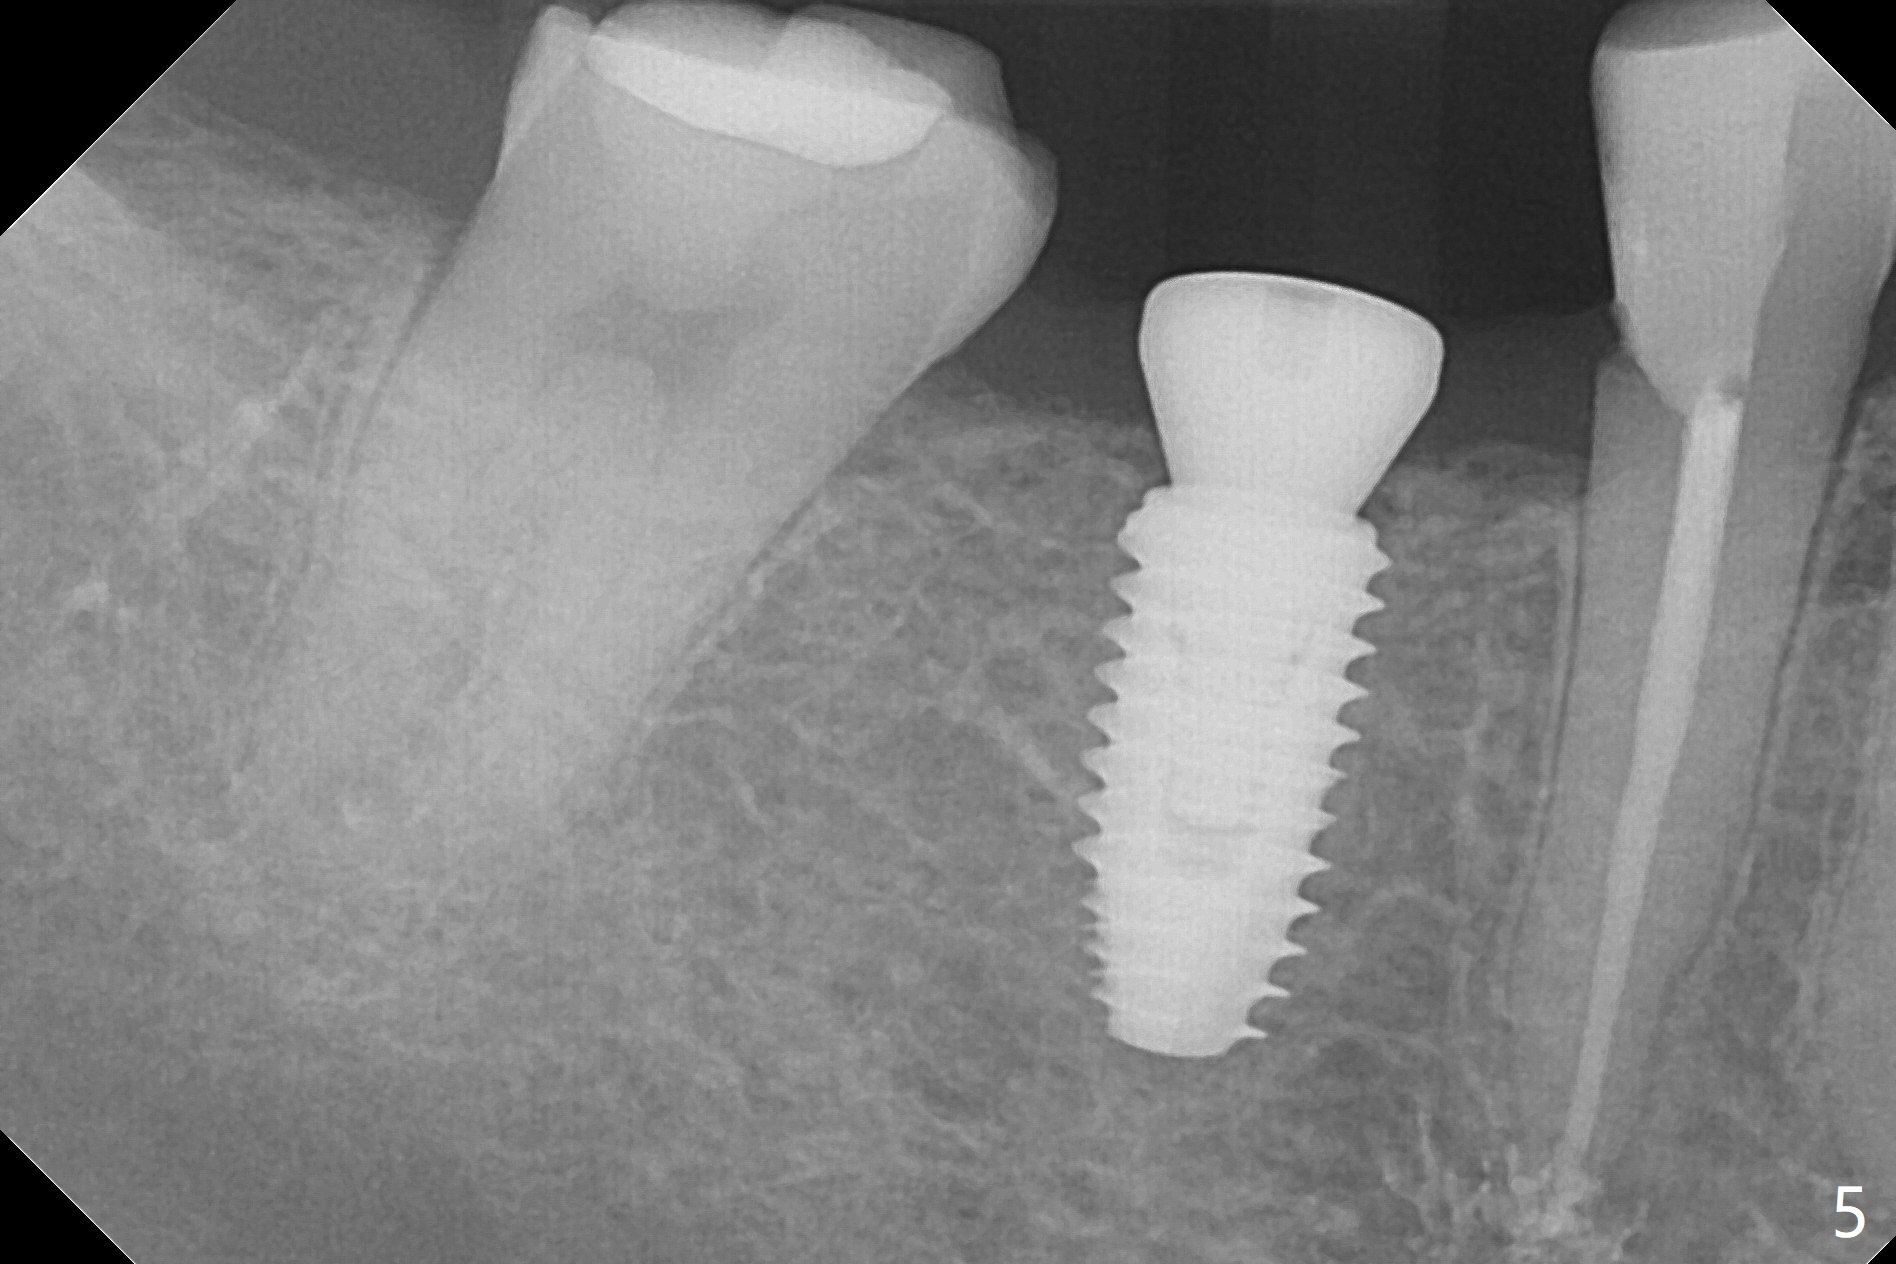

A 5x10 mm implant is placed at #30 with a surgical guide (Fig.1 *) in 10 minutes. The most amazing part of this surgery is that the guide allows you to place the implant at the precise level care-free (~ 1 mm subcrestal, Fig.2,3). Everything happens so quick that when a 5.5x3 mm healing abutment is placed (Fig.4), you are pleased to feel that the implant is stable (Fig.5). You could not ask for anymore. The fearful patient reports no postop pain. The implant is placed as planned (Fig.6, overlap image provided by the guide designer, Jennifer). The patient returns for impression nearly 2 months postop (Fig.7,8). It appears that the implant has osteointegrated without bone loss (Fig.7). The soft tissue is healthy around the just placed cementation abutment (Fig.8 (5.2x4(2) mm)). When the permanent crown is seated initially 2.5 months postop, the mesial contact is slightly tight and the occlusion is high. Bitewing shows the distal open margin (Fig.9 >). After mesial contact adjustment, the patient feels that the occlusion is better. With further occlusal adjustment, the crown is cemented without distal open margin (Fig.10). The patient returns to her home country for 3 months. The implant is doing well 3.5 months post cementation; impression is taken for #14 surgical guide.